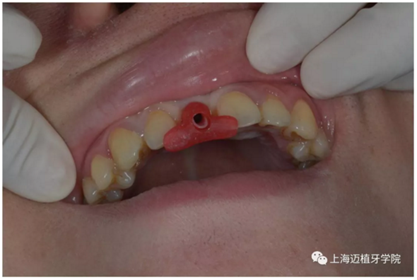

去除愈合基臺:

口內(nèi)個(gè)性化基臺: